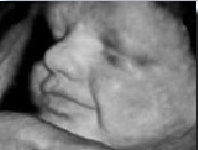

Dr. Sawant Diagnostic & Sonographic Centre - Image 1 Dr. Sawant Diagnostic & Sonographic Centre - Image 2 Dr. Sawant Diagnostic & Sonographic Centre - Image 3 Dr. Sawant Diagnostic & Sonographic Centre - Image 4